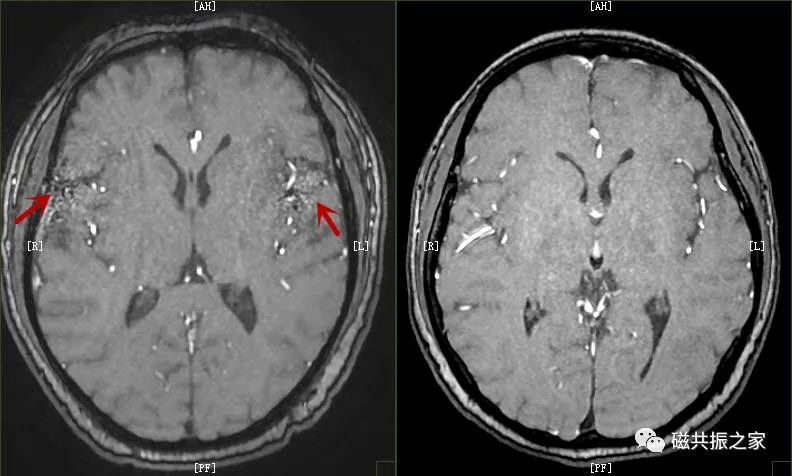

在多通道线圈的使用过程中,如选择的通道数太多则会产生另一类的并行采集伪影,如下图:

所以线圈的单元数并不是用的越多越好,很多时候单元数打开太多,不但会降低信噪比还会产生明显的并行采集伪影,常会被误认为是病变。